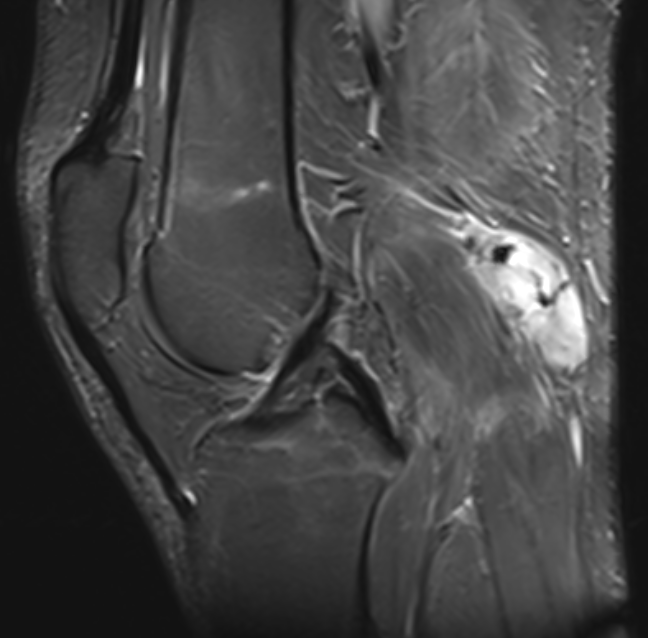

MRI

Sarcoma knee